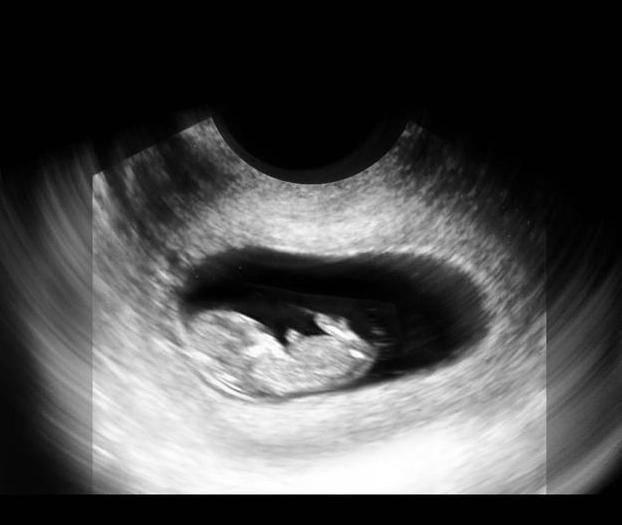

此时的胎儿继续快速发育,器官已经不是模糊一片,而是具有了鲜明的特征,比如手指脚趾已经形成,耳朵和牙齿也在发育,消化器官也开始发育了,基本都在定向地发展。

此时的宝宝可以叫做胎宝宝了,因为它已经具备很多人类的特征了,他的各个器官、肌肉和神经系统已经发育的产不多了,顾家也开始越来越坚固,从图片上看,宝宝就是迷你型的胎儿,他的各个器官开始工作了。